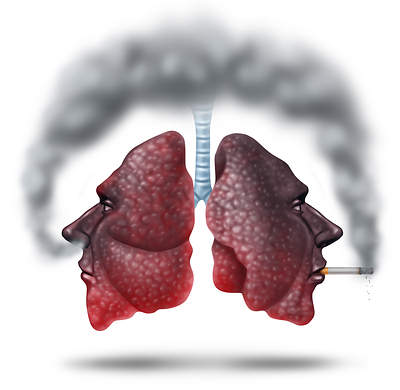

1. الأقلاع عن التدخين:

اذا كنت تدخن، فقد حان الوقت للأنتها من هذه العادة لتحسين حالة رئتيك. دخان السجائر يحتوي على آلاف المواد الكيميائية الضارة، وبعضها يمكن أن يسبب مشاكل صحية.

في الواقع، التدخين هو السبب الرئيسي لأمراض الرئة الخطيرة مثل سرطان الرئة ومرض الانسداد الرئوي المزمن.

يمكن لدخان السجائر أن يضيق الممرات الهوائية ويجعل التنفس أكثر صعوبة. حيث أنه يسبب التهاب مزمن أو تورم في الرئتين.

مع مرور الوقت يمكن لدخان السجائر أن يدمر أنسجة الرئة، وهذا بدوره يزيد من خطر الإصابة بسرطان الرئة.

إذا كنت تعاني من أي نوع من أمراض الرئة، و فعليك بالقلاع عن التدخين يمكن لذلك أن يحسن من حالتك ويمتعك بحياة افضل

يجب أن تكون مصمم على القلاع أو استشارة خبراء في ذلك.